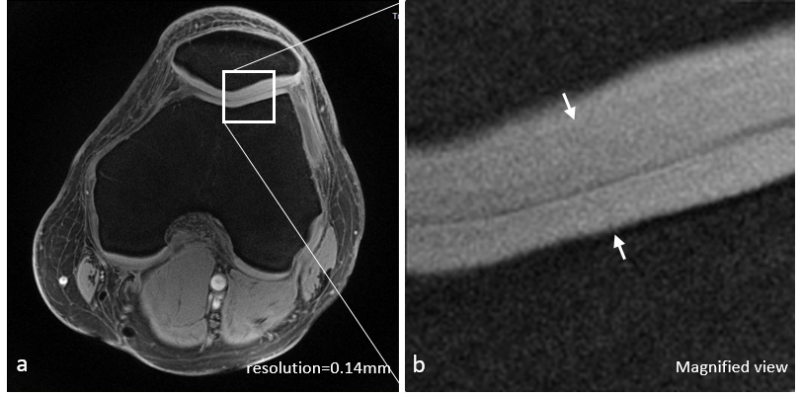

Qian's Lab for MRI at the General Labs Cloud, LLC announces a new technology that produces high resolution MRI images for the brain and knee at an ultrashort echo time (<1 ms). The high resolution UTE images can be used in clinical research to detect subclincal injuries/defects in cartilages of the knee or in parenchyma of the brain, without impact from edema fluids. The technology includes a pulse sequence and a computer program for image reconstruction. Data acquisition is based on an acquisition-weighted stack of spirals (AWSOS) pulse sequence, which is applicable to MRI systems at 3 Tesla or higher. This technology was invented by Dr. Qian and colleagues, patented in the United States (Patent No.: US7750632), and owned by the University of Pittsburgh, Pittsburgh, PA. Therefore, only lease is availabe to customers.

Figure (left): High-resolution UTE image of a healthy knee at 3T (TE = 0.6 ms, in-plane resolution = 0.14 mm, and slice thickness = 2.0 mm). Figure (right): High-resolution image of a healthy brain at 7T (TE = 1.1 ms, in-plane resolution = 0.22 mm, and slice thickness = 2.0 mm).